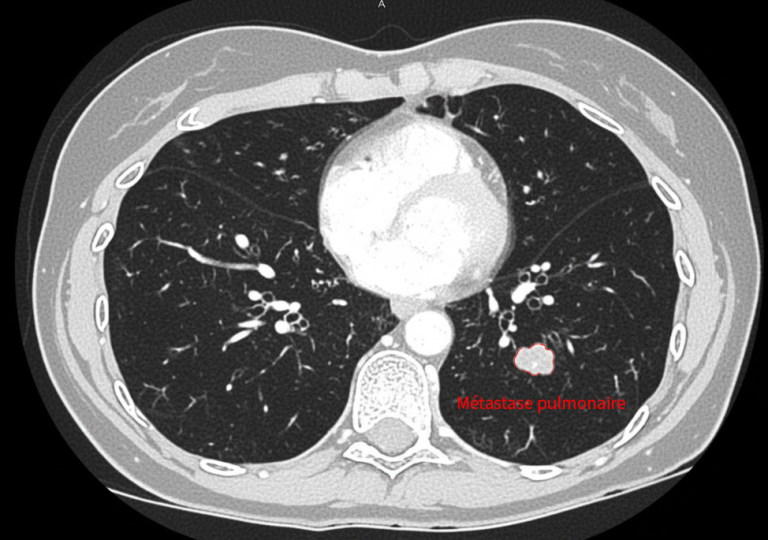

• une métastase pulmonaire de 2,5 cm, située près de structures centrales,

Traitement pulmonaire par cryoablation

La lésion pulmonaire est traitée par cryothérapie, permettant une destruction efficace tout en évitant une chirurgie lourde (lobectomie).

En images

Images du traitement des organes (poumon et foie) avant, pendant et après le traitement.